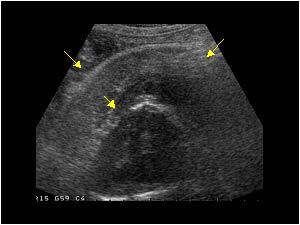

Diagnosis?

Causes?

Medullary nephrocalcinosis.

95% of cases are due to primary hyperparathyroidism, distal renal tubular acidosis (type 1), or medullary sponge kidneys.

But it can be caused by anything that causes hypercalcemia, hypercalciuria, or hyperoxaluria (others include milk alkalai syndrome, multiple myeloma, hypervitaminosis D, Cushing syndrome).